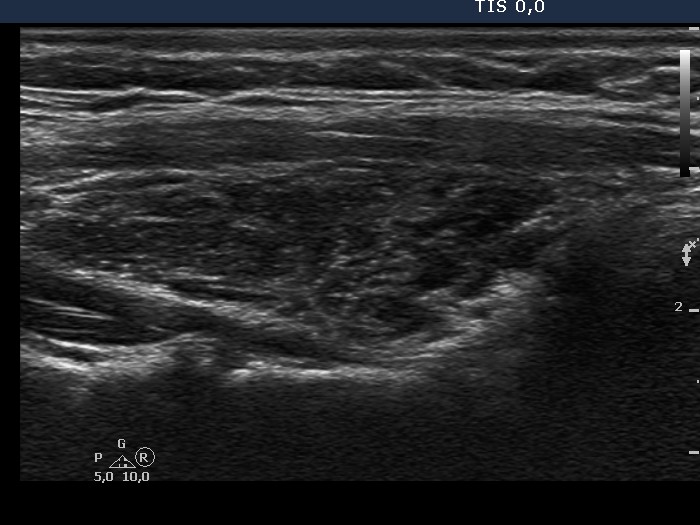

Chronic lymphocytic thyroiditis - Case 36. |

Clinical data: a 35-year-old woman with hypothyroidism replaced with 100 ug levo-tiroxin was referred for evaluation of thyroid nodules.

Ultrasonography: there were several circumscribed areas which in fact did not fit nodules. These are active foci of autoimmune thyroiditis.

Cytological report: benign Hashimoto's thyroiditis.